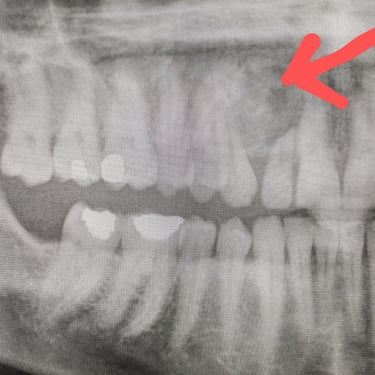

Dientes impactados

Los dientes impactados son dientes que no pueden erupcionar correctamente debido a la falta de espacio o a una obstrucción.

Los pacientes pueden notar que un diente no ha salido, aunque debería haberlo hecho. Esta condición es común con las muelas del juicio y los caninos superiores.

El tratamiento puede incluir la extracción del diente impactado o la creación de espacio para permitir su erupción.